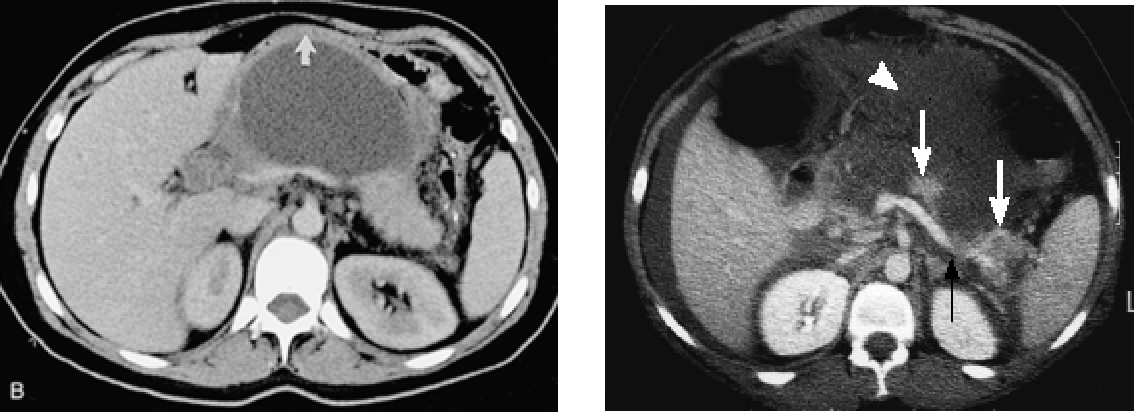

A:38岁,女患,急性间质水肿性胰腺炎,白箭头所示左肾周前间隙急性胰周液体积聚。胰腺完全强化,增大,但由于水肿导致强化不均匀。急性胰周液体积聚呈液体密度,无囊壁包裹。B:几周后,随访CT发现急性胰周液体积聚完全吸收,残留极少胰周脂肪毛糙影。

(2)CT对胰腺炎的严重程度有较大价值

CT-胰腺实质密度增高或降低,体积增大,胰周浸润。

增强CT-清楚显示胰腺坏死区域、范围